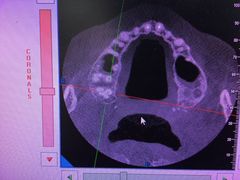

• 上海中医药大学附属曙光医院(东部)

• -上海中医药大学附属曙光医院(东部)

BB1380 | 18-03-06